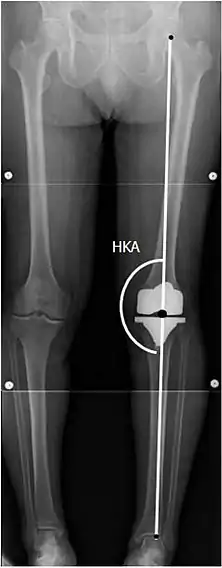

![]() |

Angles commonly measured before knee replacement surgery: |

To indicate knee replacement in case of osteoarthritis, its radiographic classification and severity of symptoms both should be substantial. Such radiography should consist of weightbearing X-rays of both knees: AP, lateral, and 30 degrees of flexion. AP and lateral views may not show joint space narrowing, but the 30-degree flexion view is most sensitive for narrowing. Full-length projections also are used in order to adjust the prosthesis to provide a neutral angle for the distal lower extremity. Two angles used for this purpose are:

- Hip-knee-shaft angle (HKS),[10] an angle formed between a line through the longitudinal axis of the femoral shaft and its mechanical axis, which is a line from the center of the femoral head to the intercondylar notch of the distal femur.[12]

- Hip-knee-ankle angle (HKA),[11] which is an angle between the femoral mechanical axis and the center of the ankle joint.[12] It is normally between 1.0° and 1.5° of varus in adults.[13]